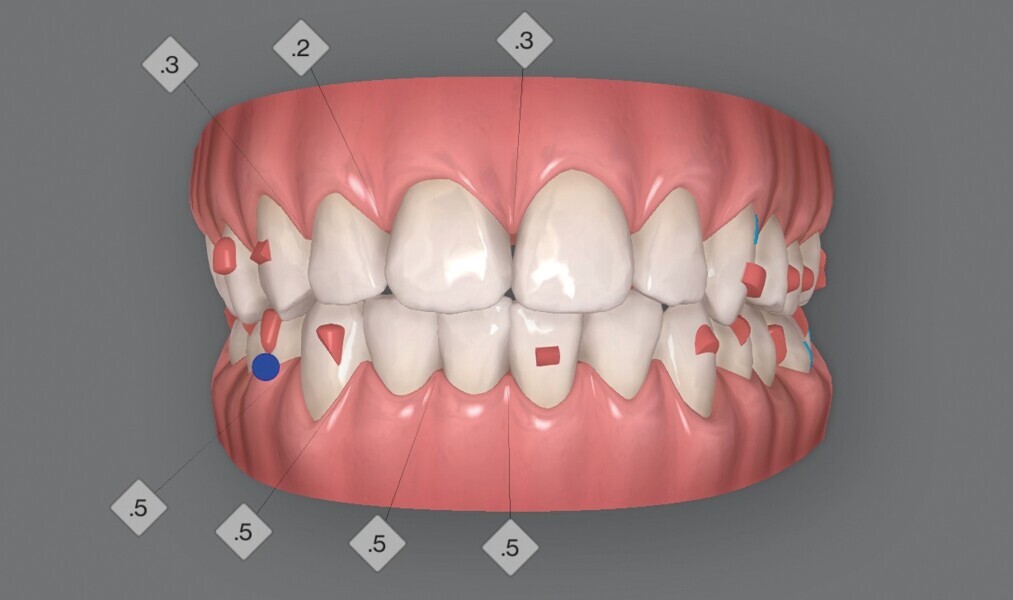

Fig. 5a : Plan supplémentaire du traitement par aligneurs conçu par ClinCheck (début).

Fig. 5b : Plan supplémentaire du traitement par aligneurs conçu par ClinCheck (début).

Fig. 5c : Plan supplémentaire du traitement par aligneurs conçu par ClinCheck (début).

Figs. 5d : Plan supplémentaire du traitement par aligneurs conçu par ClinCheck (début).

Fig. 5e : Plan supplémentaire du traitement par aligneurs conçu par ClinCheck (début).

La première série d’aligneurs permet de réaliser les mouvements orthodontiques programmés dans le logiciel avec une efficacité supérieure à 95 % (Fig. 5), et d’obtenir une forme anatomique des arcades, une correction de l’occlusion croisée et de la relation de classe II du côté gauche, une réduction de l’encombrement dans le maxillaire et la mandibule, et un alignement des lignes médianes. Au terme de cette première phase, les observations cliniques indiquent une infraclusion postérieure, résultant de l’intrusion passive des dents postérieures due à l’épaisseur du matériau de l’aligneur, et des contacts antérieurs prématurés. Quelques mouvements dans la zone incisive mandibulaire sont encore nécessaires pour terminer le traitement, et un deuxième jeu d’aligneurs est donc prévu pour éliminer les problèmes et finaliser la position des dents.